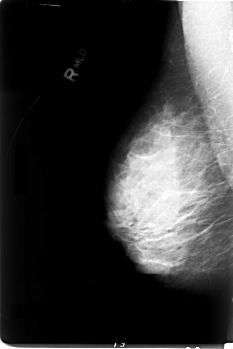

RIGHT_CC LINES 5928 PIXELS_PER_LINE 3944 BITS_PER_PIXEL 12 RESOLUTION 50 NON_OVERLAY

RIGHT_MLO LINES 5928 PIXELS_PER_LINE 3952 BITS_PER_PIXEL 12 RESOLUTION 50 NON_OVERLAY